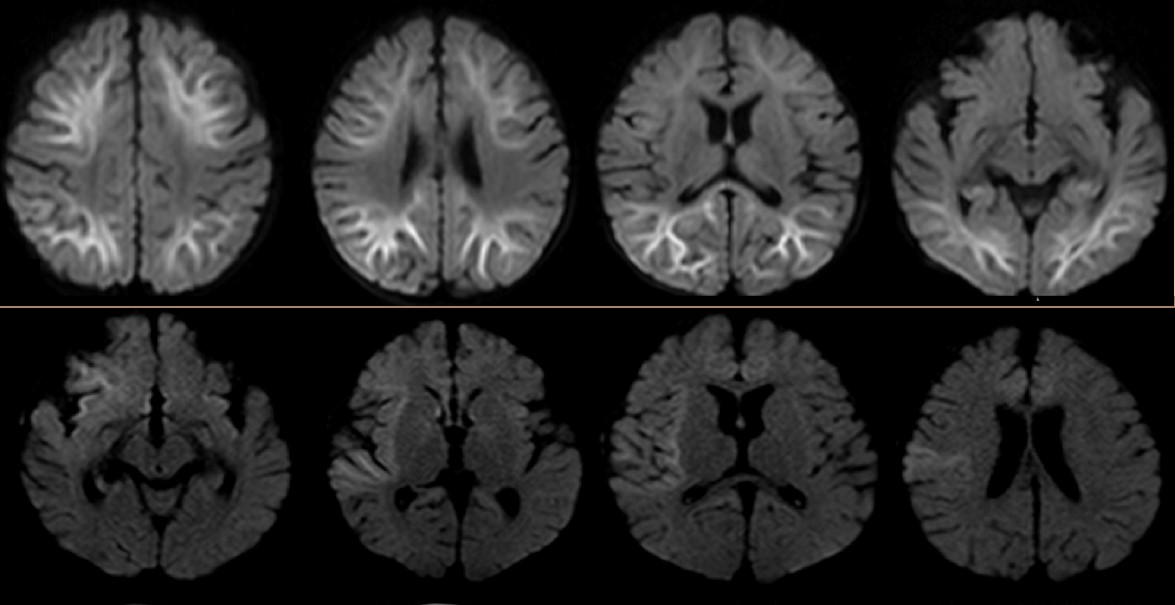

The patient had had an initial seizure onset at 5 months of age, and before the current hospitalization, he had previously been admitted twice to the hospital for worsening seizures. Results of extensive laboratory evaluations for epilepsy—including chromosomal microarray, cerebrospinal fluid (CSF) neurotransmitters, pyruvate, lactic acid, and metabolic panels including urine organic acids, acylcarnitine profile, and plasma amino acids—had been unremarkable. Brain magnetic resonance imaging (MRI) abnormalities involving distinct regions—deep posterior subcortical white matter and frontal, insular, temporal areas—were noted in each of the previous 2 admissions, respectively (Figure 1). The etiology of the epilepsy and developmental delay remained unclear. There was no concern for infection.

Figure 1. Top: Abnormal restricted diffusion involving both cerebral hemispheres with predominant involvement of deep and subcortical white matter. Bottom: Abnormal restricted diffusion involving the right insular region, right frontal region, right temporal operculum, and right amygdala of the brain.